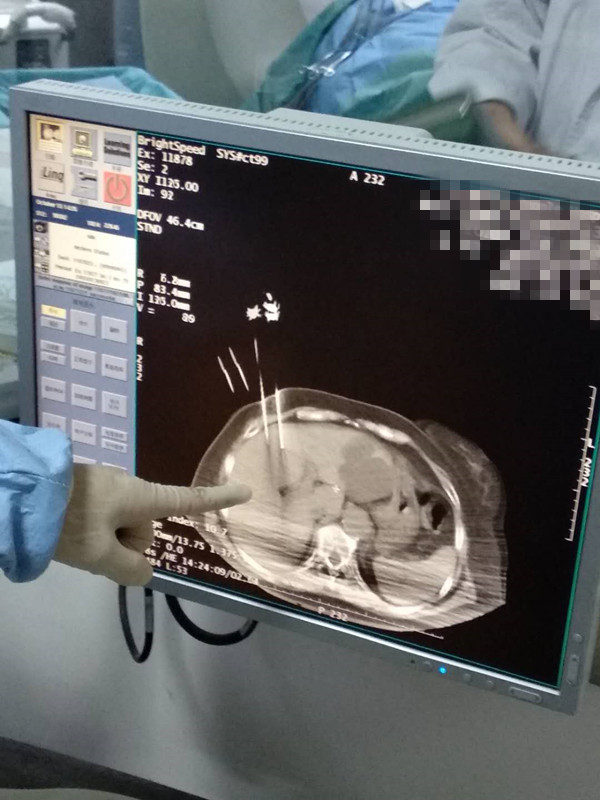

73岁患者肝部氩氦刀冷冻消融